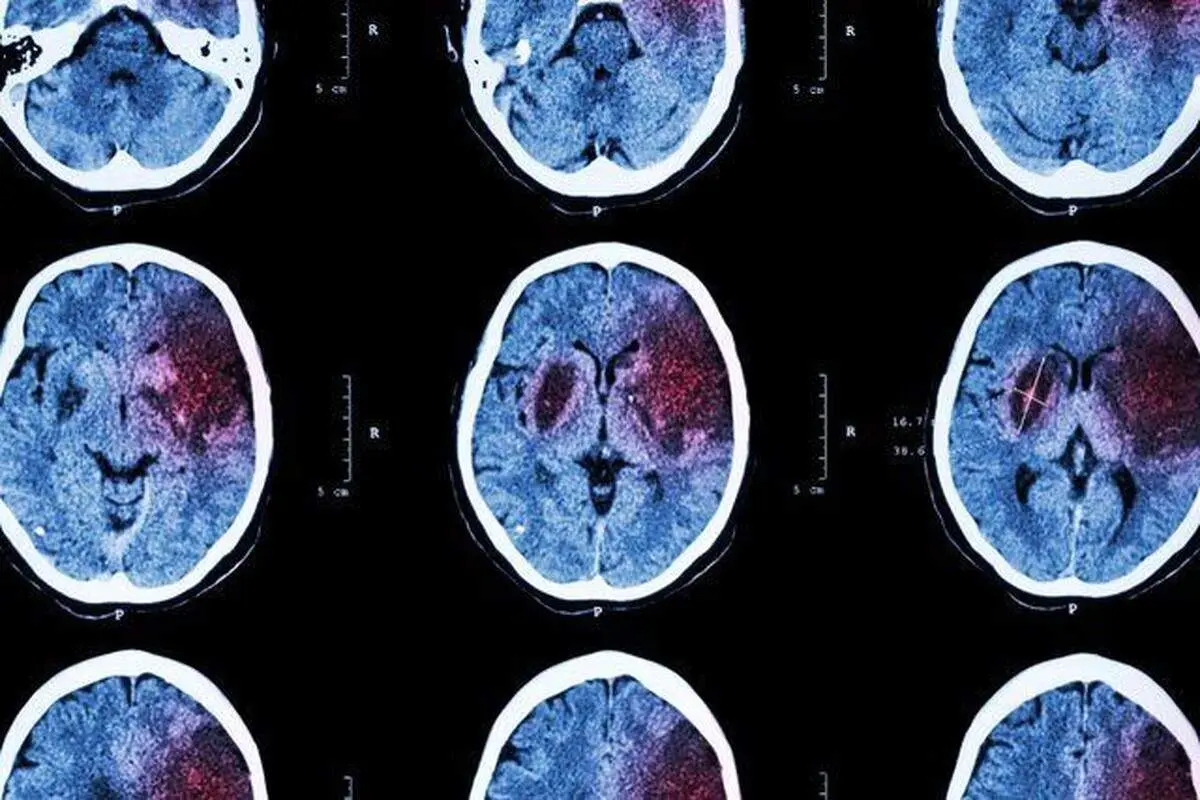

پارسینه: از طریق تغییر سبک زندگی می توان از بروز بسیاری از موارد سکته مغزی پیشگیری کرد. با بی‌تحرکی ، تغذیه ناسالم و زندگی پرتنش و پر استرس روزمره ، خطر سکته مغزی نیز افزایش می‌یابد.

پزشکان می‌گویند با «انتخاب سبک زندگی سالم و کنترل عوامل خطر» می‌توان از بروز سکته مغزی پیشگیری کرد.